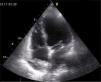

A doente manteve‐se bem durante o pós‐operatório, necessitando de suporte ventilatório durante três dias. Após cirurgia, foi realizado novo ciclo de seis semanas de antibioticoterapia dirigida, com franca regressão dos parâmetros inflamatórios. TC de tórax com contraste endovenoso (não realizada ressonância magnética por dificuldades técnica, dados os artefactos resultantes dos fios de sutura) após estas seis semanas mostrou uma aorta ascendente dilatada (47x49mm), mas sem evidência de soluções de continuidade ou pseudoaneurismas (Figura 4).